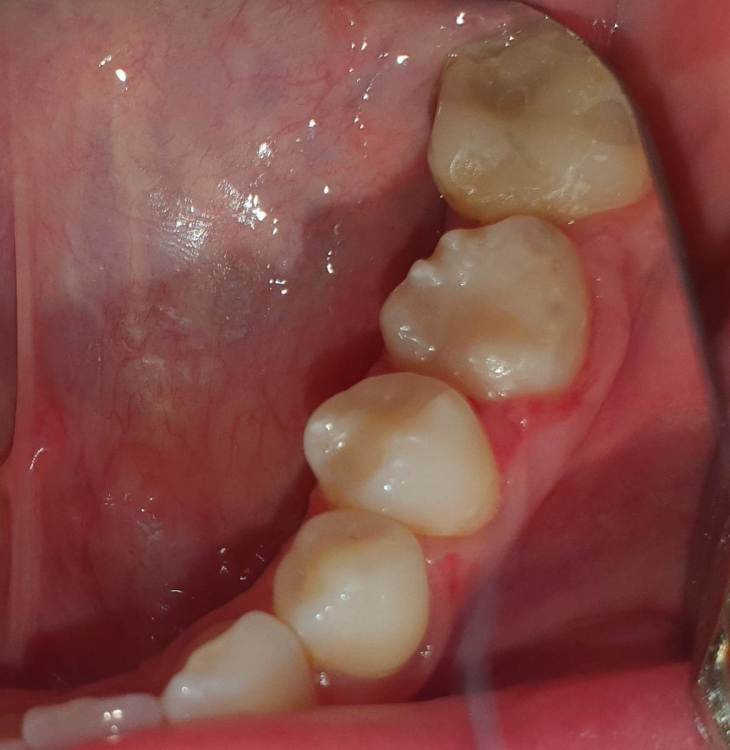

Dr.Deletle Опубликовано 22 июля, 2023 Поделиться Опубликовано 22 июля, 2023 (изменено) Этот кейс интересен тем, что у пересаживаемого 2.8 полностью сформированы корни. Пациент Н., 35лет, зуб 3.6 подлежит удалению по терапевтическим показаниям. Донором был выбран зуб 2.8. Фото №1, 2 - ситуация ДО на фото и срезе КЛКТ Фото №3 - планирование на реконструкции ОПТГ из КЛКТ Фото №4 - шаблон зуба 2.8 Фото №5, 6 - операция, удален 3.6, припасован шаблон, пересажен 2.8 (фиксирован швами и шиной к 3.7) Фото №7 - КТ сразу после пересадки Фото №8, 9 - депульпирование пересаженного 2.8 через 2 недели Фото №10 - снятие шины через 2нед после пересадки Фото № 11, 12, 13 - состояние в полости рта и на срезе КТ через год после пересадки, видно сформированное периодонтальное пространство, здоровая костная ткань, жалоб у пациента нет, полноценно жует как обычным зубом Изменено 22 июля, 2023 пользователем Dr.Deletle 4 3 Ссылка на комментарий